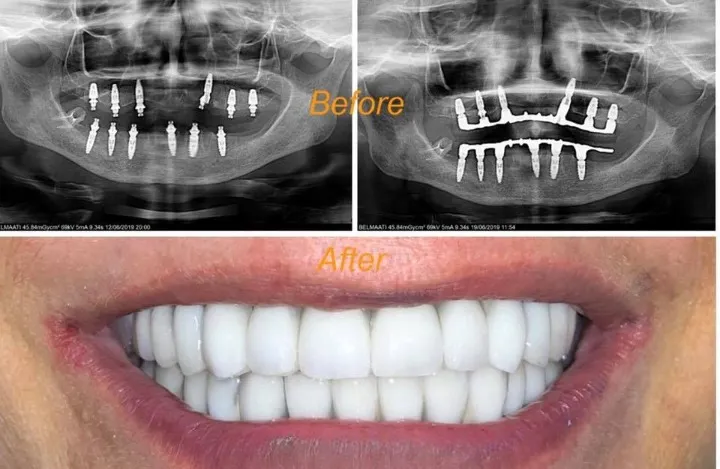

Traitement Parodontite Avancée

Thérapie non-chirurgicale et chirurgicale pour éliminer l'infection, stopper la progression du déchaussement et stabiliser les dents mobiles. Protocole personnalisé selon le stade de la maladie.